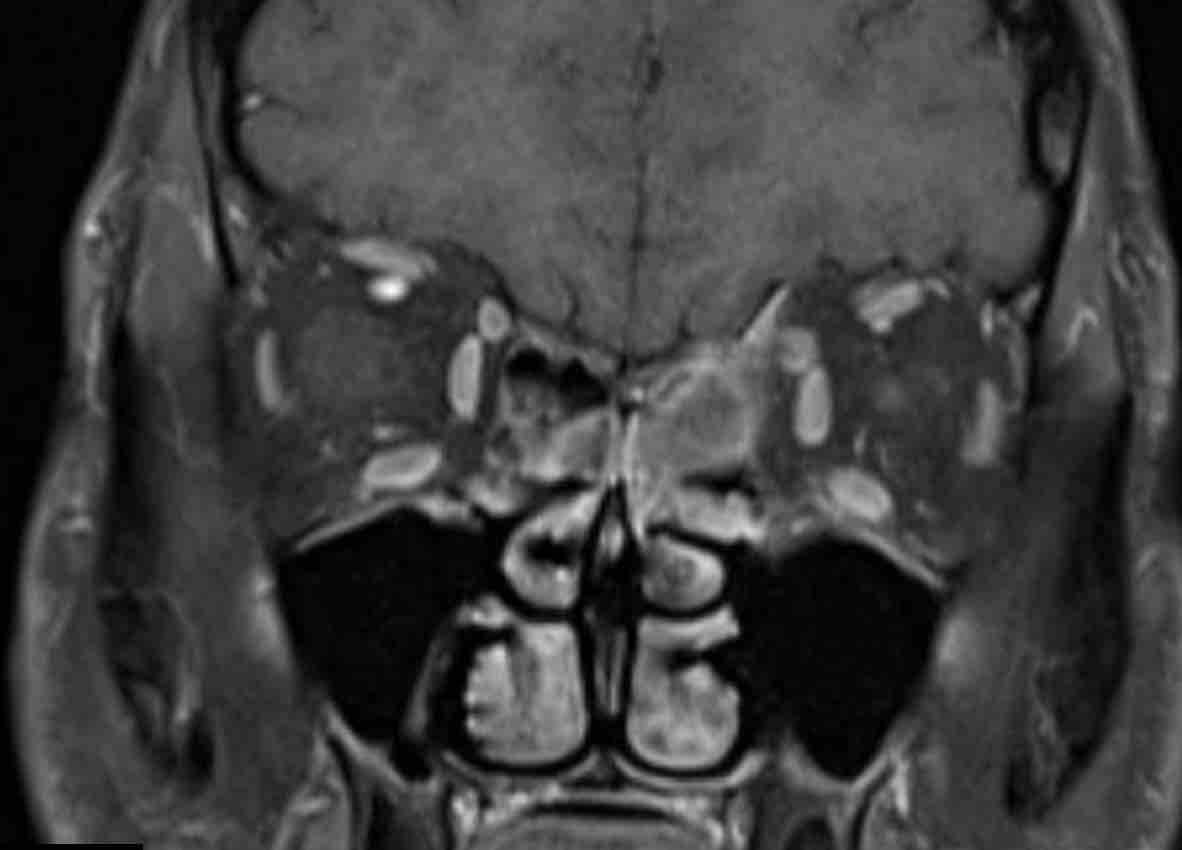

Các hình ảnh này của một bệnh nhân nam 16 tuổi với biểu hiện lồi mắt và chảy máu mũi.

Trên các hình ảnh này, có một tổn thương phá hủy xương với xâm lấn vào hốc mắt.

U xơ mạch máu vị thành niên luôn xuất phát từ hốc mũi phía sau và có tâm tổn thương xung quanh lỗ bướm khẩu cái và hố chân bướm khẩu cái.

Lưu ý rằng hố không bị xâm lấn và tâm của tổn thương không nằm ở lỗ bướm khẩu cái và hố chân bướm khẩu cái.

Điều này khiến chẩn đoán ban đầu là u xơ mạch máu vị thành niên trở nên khó có khả năng.

MRI cho thấy một khối u phá hủy một bên với hạn chế khuếch tán rõ rệt (giảm tín hiệu trên bản đồ ADC).

Như vậy, chúng ta có ba dấu hiệu cảnh báo.

Hạn chế khuếch tán là một lập luận khác chống lại chẩn đoán u xơ mạch máu vị thành niên, vì một tổn thương mạch máu sẽ không gây ra hạn chế khuếch tán.

Có xâm lấn vào hốc mắt và cả vào phần mềm phía trước của má (mũi tên).

Sinh thiết được thực hiện và cho kết quả là u cơ vân (rhabdomyosarcoma), được điều trị bằng hóa trị liệu.